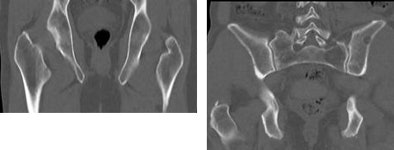

![]() |

| Thin-section whole-body MDCT in a low-dose 50 mAs protocol (41-year-old male, right) performed as well as a standard 100 mAs protocol (54-year-old male, left) for detecting osteolytic lesions. Mean image noise (24 HU) was higher for the low-dose images (12 HU), but image quality was rated excellent for both groups, and the radiation dose was far lower in the 50 mAs protocol. Images courtesy of Dr. Sonja Buhmann. |

The average cost of the CT exam (320 euros) fell between that of radiography (230 euros) and MRI (590 euros). While MRI is the gold standard, CT offers high-resolution imaging and display of the trabecular structure. The CT exam was also faster, and perhaps most important, CT picked up every lesion detected by MRI, Buhman said.

"All osteolytic lesions that were primarily detected on the gold-standard MRI were also detected using 50 mAs as well as 100 mAs CT," she said. Considering the accuracy and the low effective radiation dose, Buhman said, it may be advisable to choose low-dose CT in favor of radiography for initial skeletal assessment in patients with multiple myeloma. Even at 50 mAs, CT still provided good image quality.